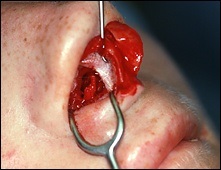

Mielőtt nagyobb acanthion. Ez az, amit úgy néz ki, a művelet során. Az ábrán a jobb ez sárga színű. Acanthion columella található, közvetlenül alatta, ahol a felső ajak határos az alapja az orrát.

Része a gerinc, amelyeket el kell távolítani jelzi a kék vonalon. Removal végezzük vésővel.

A felső és az alsó képen látható két legkiemelkedőbb nazális gerinc, a jobb kilátás bővítették segítségével horgokat.